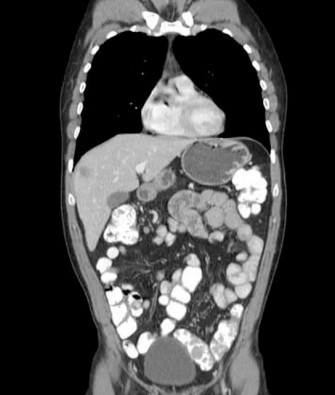

- Examen coloscopique : il est essentiel pour identifier les polypes colorectaux et évaluer leur nombre et leur taille.

- Neuroimagerie : l'IRM ou la tomodensitométrie sont utilisées pour détecter et évaluer les tumeurs du SNC, fournissant des informations essentielles sur la taille, l'emplacement et le type.